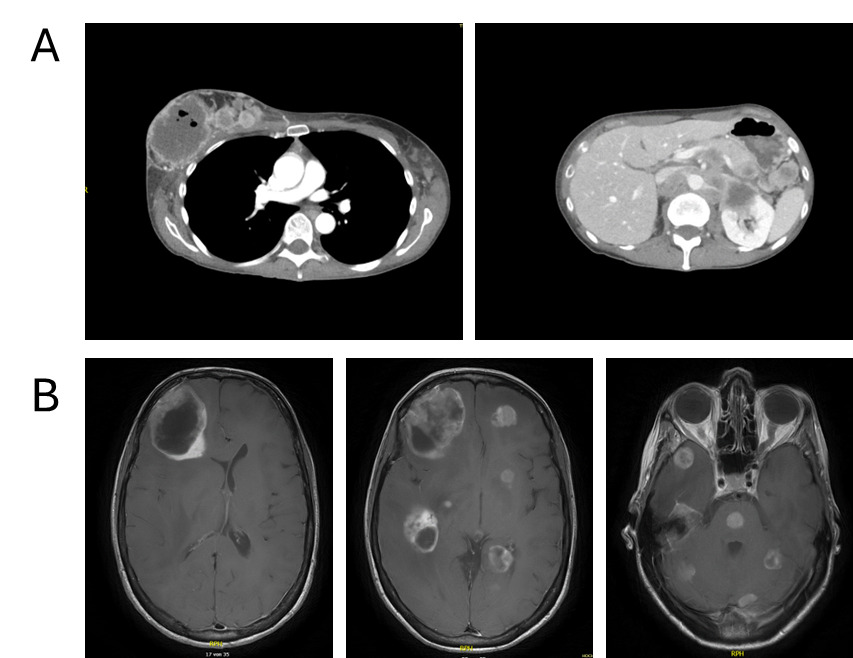

Contrast-enhanced computed tomography (CT) of the thorax and abdomen revealed a right breast mass measuring up to 7 cm, characterized by central necrosis, intralesional gas, peripheral contrast enhancement and cutaneous infiltration (Figure 2A). Extensive lymphadenopathy was present in the bilateral axillary, cervical, supraclavicular and mediastinal regions. Widespread abdominal involvement was noted, including bulky retroperitoneal and pararenal lymphadenopathy with infiltration of the renal hilum and Gerota’s fascia, encasement of major abdominal vessels without occlusion, pancreatic and bilateral adrenal lesions, peritoneal nodules and minimal ascites. No pulmonary, hepatic or suspicious osseous metastases were detected. Overall, the clinical findings were consistent with advanced metastatic breast cancer originating from the right breast and presenting as a disseminated malignancy.

Emergency hospitalization was necessitated due to a rapid deterioration of the patient’s general condition and significant neurological deficits, specifically characterized by somnolence, disorientation and a loss of decisional capacity. Contrast-enhanced CT of the neurocranium revealed multiple (at least 12) supra- and infratentorial intracranial lesions, some partially cystic, associated with extensive perifocal edema, significant mass effect and a leftward midline shift of up to 1.1 cm, with subfalcine and incipient uncal herniation. A metastasis-suspicious left parietal osseous lesion with epidural and subgaleal extension was also identified. Subsequent magnetic resonance imaging (MRI) confirmed extensive cerebral involvement with more than 20 intradural metastases in the frontal and temporal lobes, cerebellum, basal ganglia and pons (Figure 2B). Additional metastatic sites included the left parietal calvarium with extraosseous extension, as well as in the right parotid gland and right masticator space.